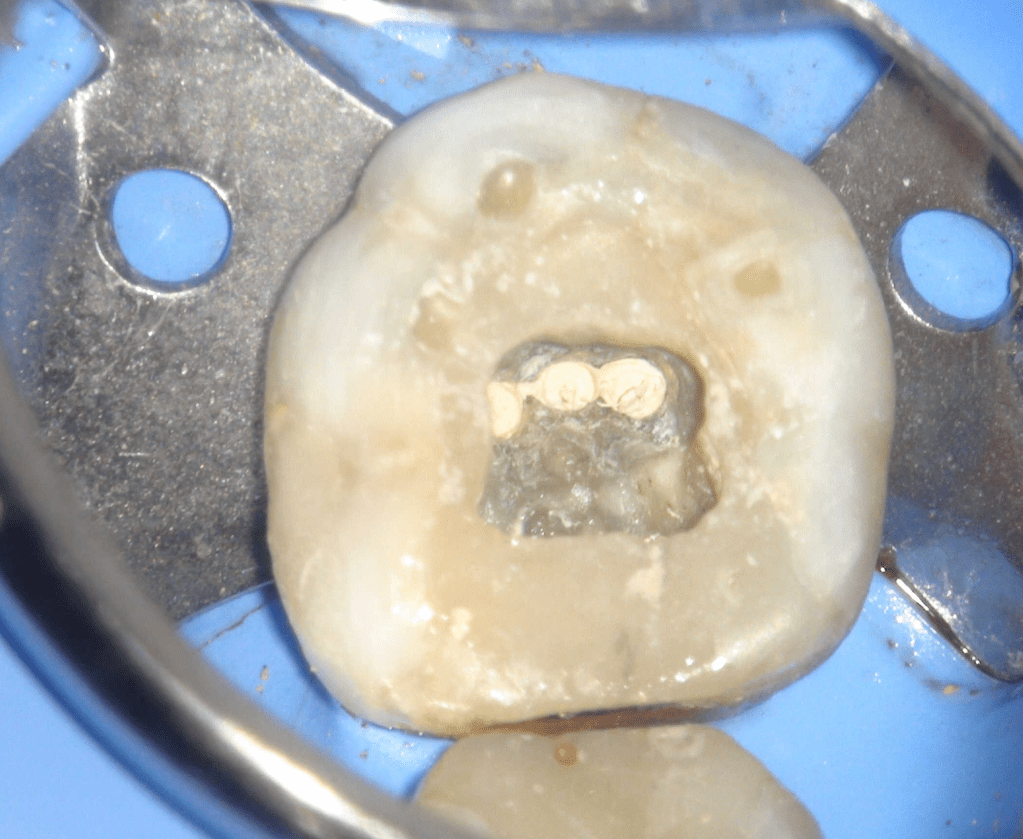

Pulpotomía biodentine + reco preendio